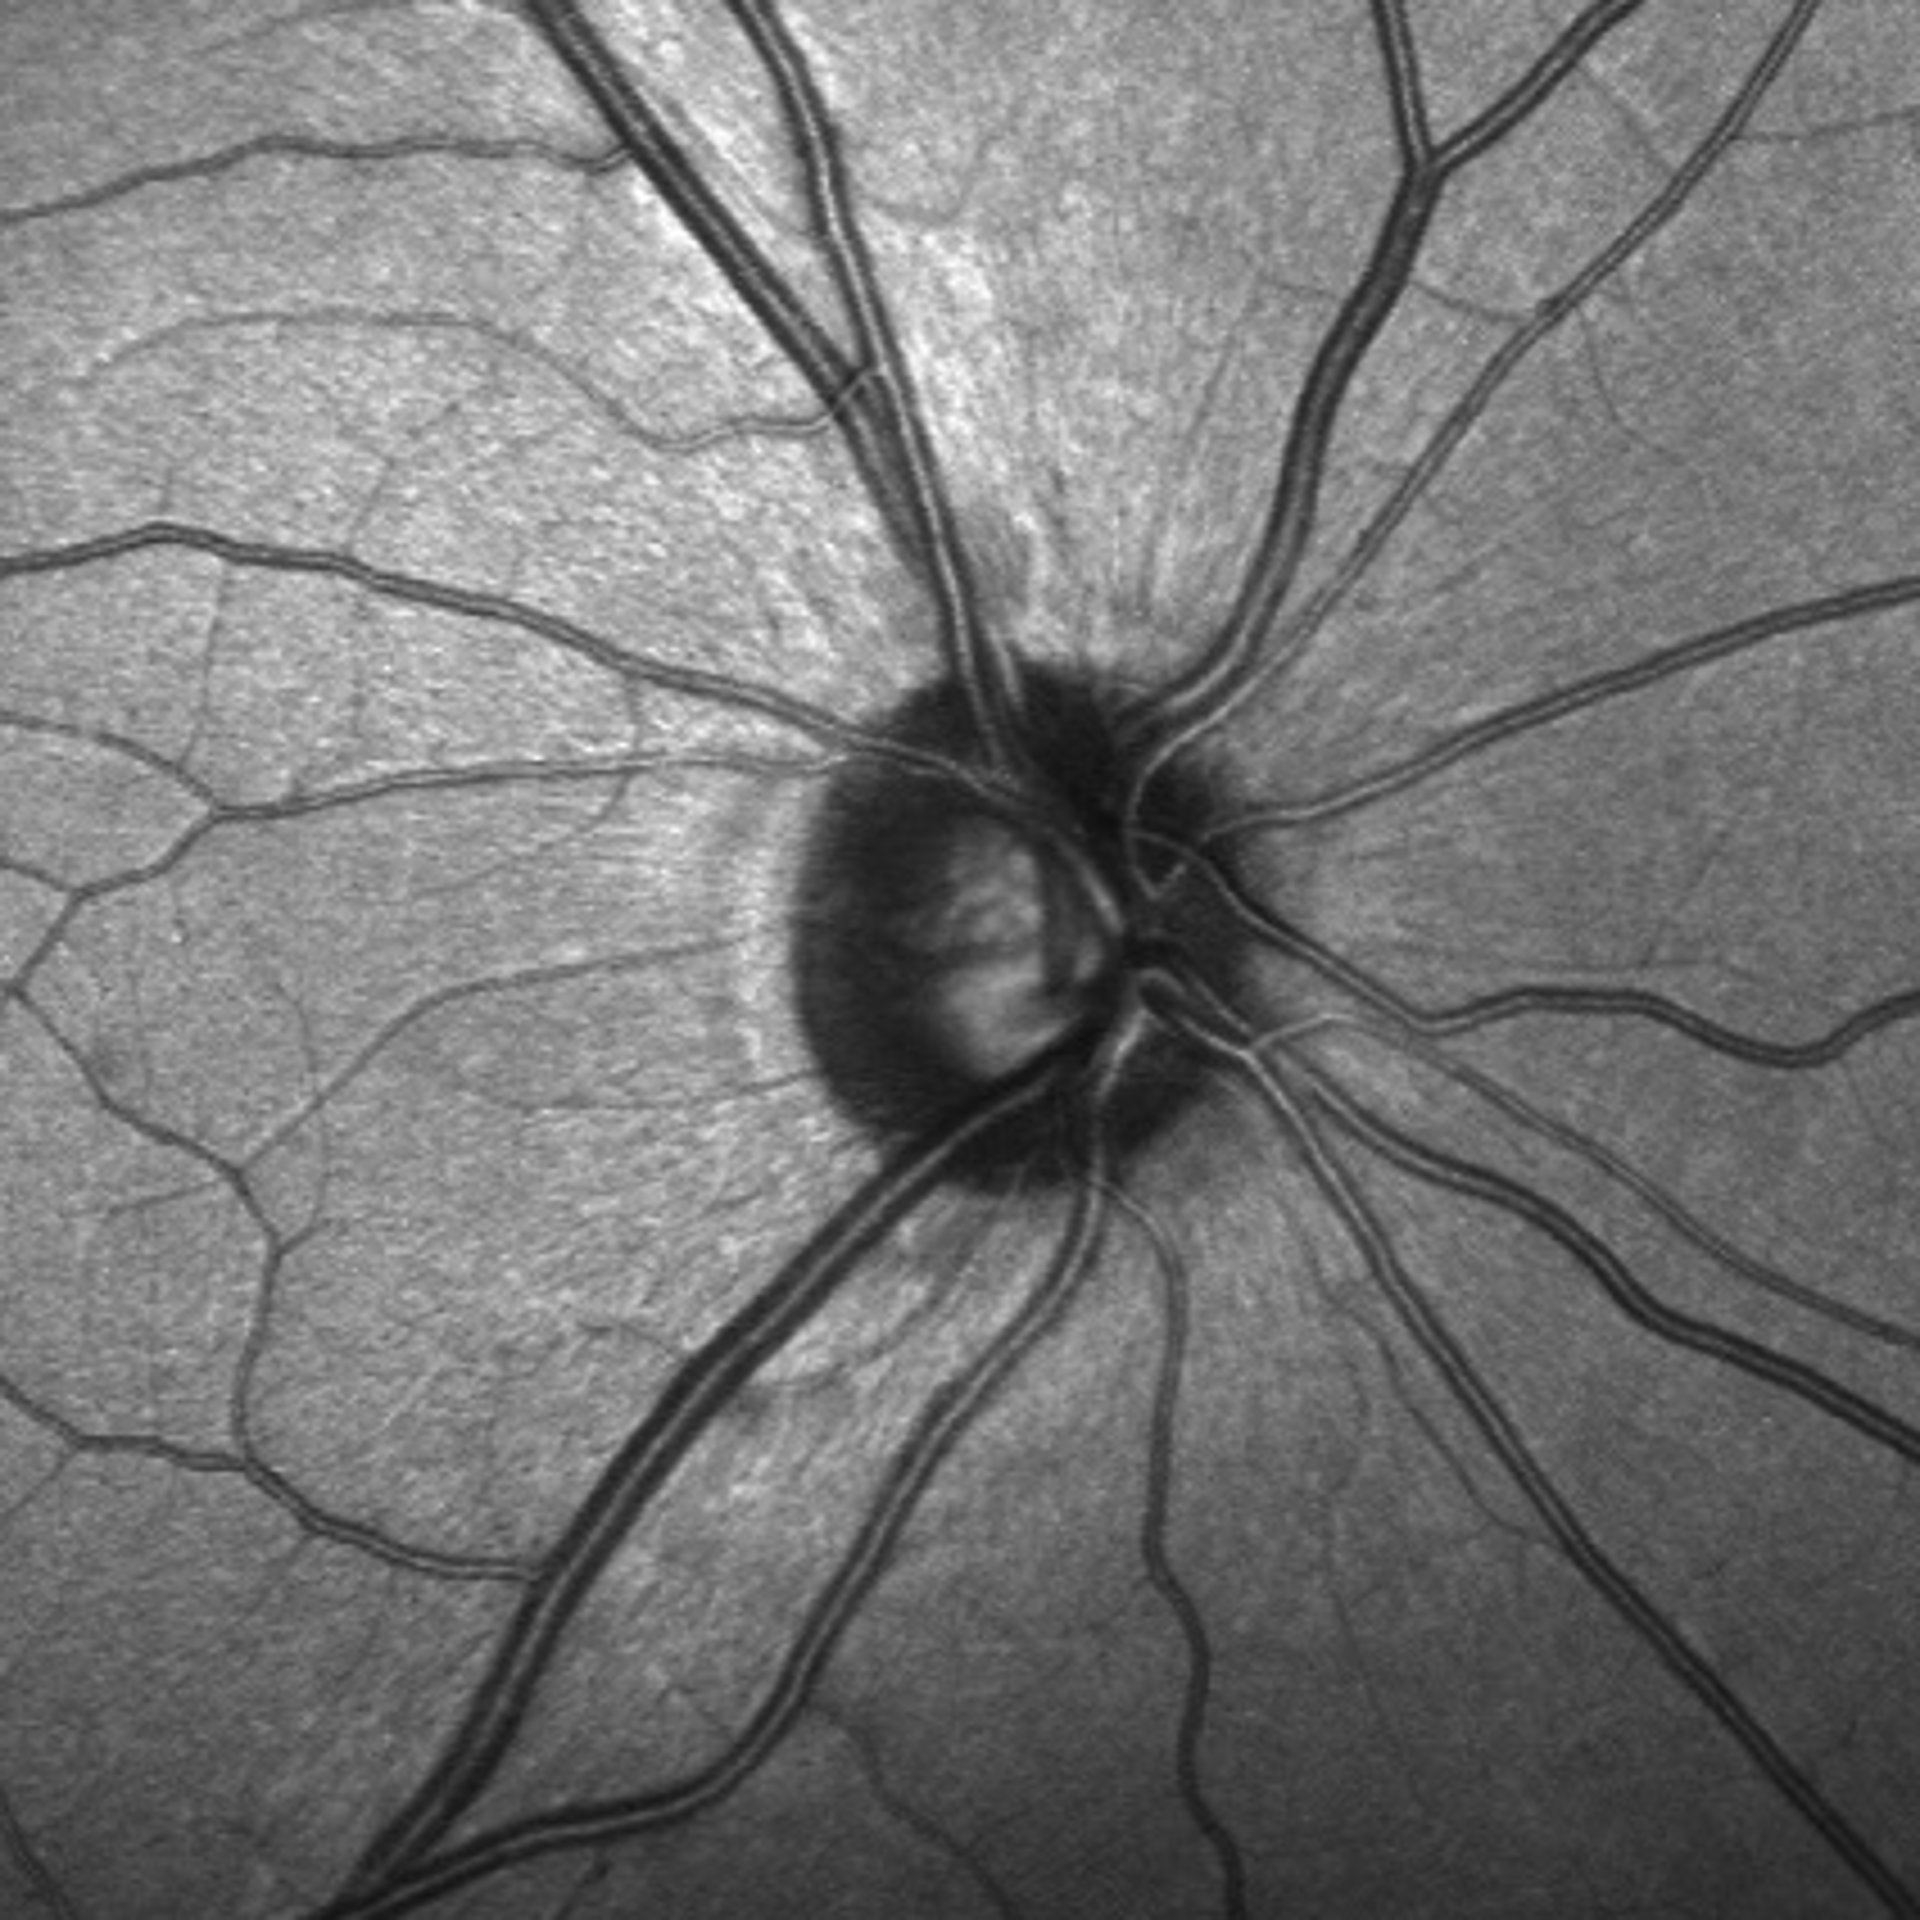

Investigadores de la Facultad de Medicina de la Universidad de Maryland (Estados Unidos) han identificado por primera vez células madre en la región del nervio óptico, que transmite señales del ojo al cerebro.

Para hacer el descubrimiento de la investigación, examinaron una estrecha banda de tejido llamada lámina del nervio óptico. Menos de 1 milímetro de ancho, la lámina se encuentra entre el tejido de la retina sensible a la luz en la parte posterior del ojo y el nervio óptico. Las largas fibras de células nerviosas se extienden desde la retina a través de la lámina, hasta el nervio óptico. Lo que los investigadores descubrieron es que las células progenitoras de la lámina pueden ser las responsables de aislar las fibras inmediatamente después de que salen del ojo, apoyando las conexiones entre las células nerviosas en el camino hacia el cerebro.

Las células madre en el nicho de la lámina bañan estas extensiones de neuronas con factores de crecimiento, así como ayudan en la formación de la vaina aislante. Los investigadores pudieron confirmar la presencia de estas células madre utilizando anticuerpos y animales genéticamente modificados que identificaron los marcadores de proteína específicos en las células madre neuronales.